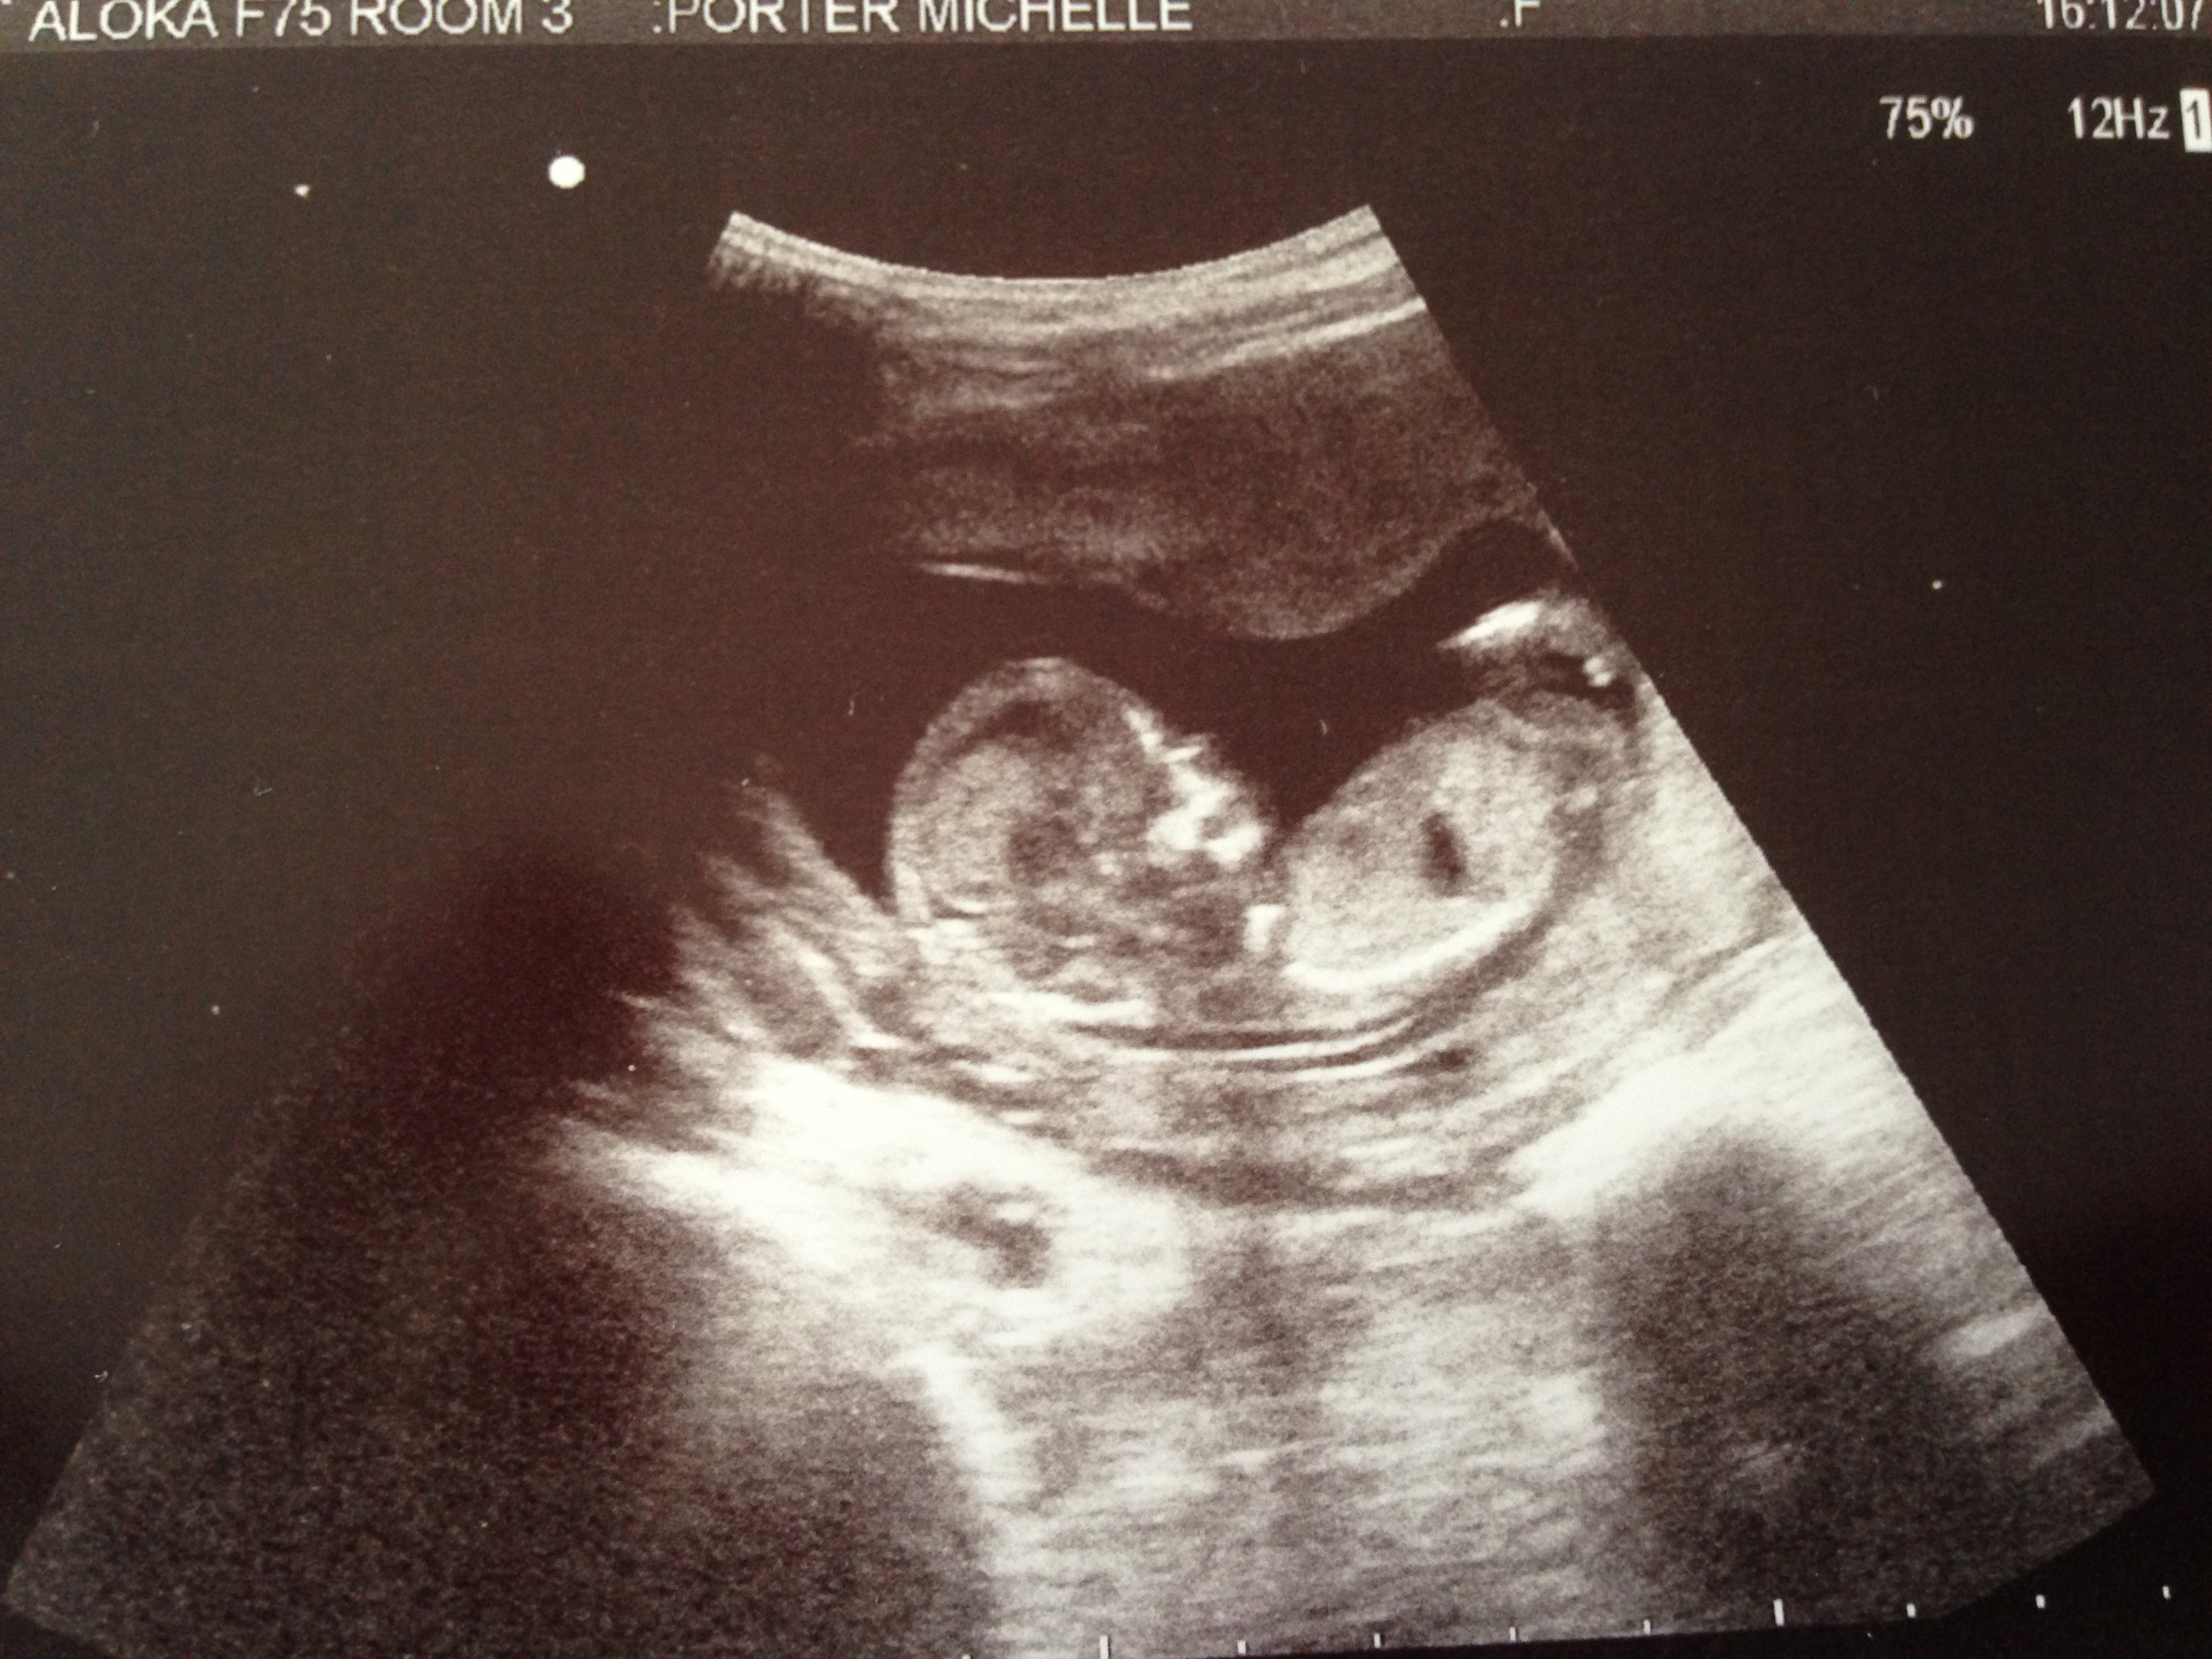

Hi any ideas from these pictures? Attachment 17533

Can't see nub sorry xx

MAYBE girl....unfortunately there is not a real clear pic of the nub....but since you were in your 13th week, what I can see looks flat! Congrats in baby :)

What is the nub bit you can see on my pic? I thought I could see the nub clearly but then someone said I was looking at the hip bone (ha ha).

The nub bit I THINK I am seeing on your scan pic is the brighter white line.....but I'm unsure as there is a leg there and its no overly clear :(